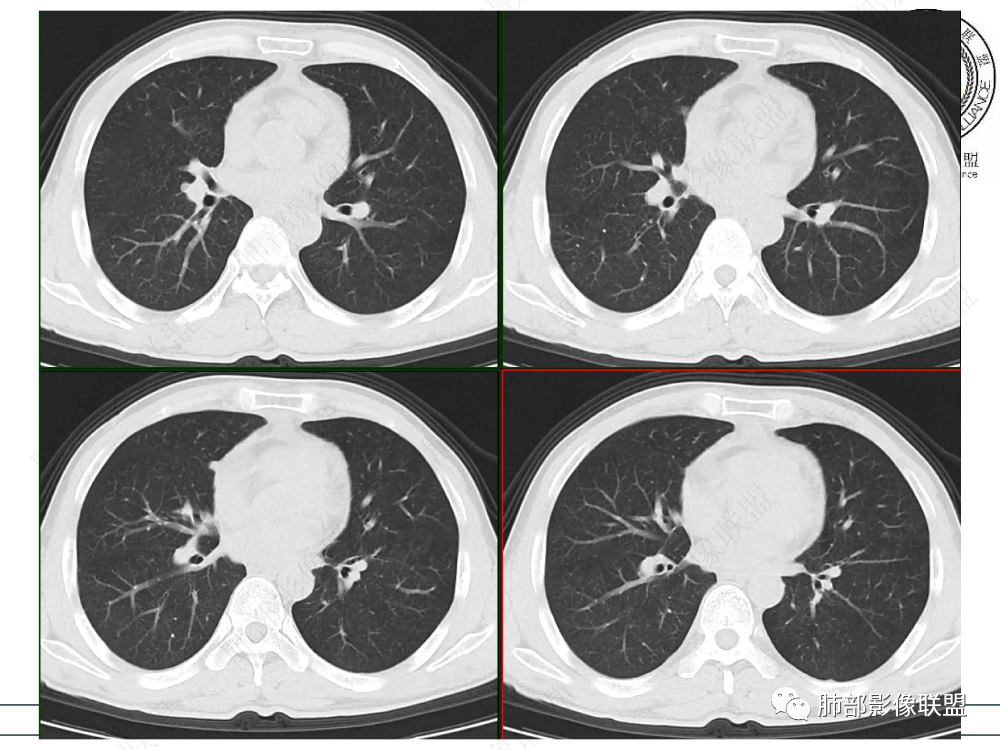

2.影像表现:前上纵隔较大肿块,密度不均,形态不规则,边界不清,有结节样突起,脂肪间隙显示不清。病灶侵犯左无名静脉及上腔静脉,其中左无名静脉闭塞(胸背部侧支循环明显,亦表明回流受阻)。增强后轻中度不均强化。坏死边界欠清晰。可见心包积液,提示心包受侵犯。右侧上叶及纵隔胸膜下结节影,疑胸膜肺转移可能。胸骨柄后缘皮质不完整,疑骨质破坏(未提供骨窗及矢状位图像)。左锁骨上可见肿大淋巴结。